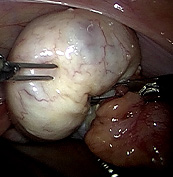

Laparoskopische Myomenukleation

Bei "Myomen" handelt des sich um gutartige "Muskelknoten", die am häufigsten in oder an der Gebärmutter vorkommen. Anzahl, Größe und die genaue Lage können dabei stark variieren Myome treten häufig ohne Symptome auf, dass heißt, sie verursachen nicht unbedingt Beschwerden. Es besteht dann keine zwingende Notwendigkeit zur Operation. Typische, durch Myome verursachte Beschwerden sind starke, häufig auch schmerzhafte Menstruationsblutungen. Mit zunehmender Anzahl und Größe der Myome kann sich die Gebärmutter insgesamt deutlich ausdehnen, so dass ein "Druck" oder Schmerz im Unterbauch entsteht. Abhängig von Lage, Größe und Anzahl der Myome können diese unter Umständen die Entstehung einer Schwangerschaft verhindern oder ein Grund für eine Fehlgeburt sein. Myome, die deutlich an Größe zunehmen, oder die Symptome verursachen, sollten operiert werden. Verschiedene nicht operative Behandlungsmethoden zeigen häufig nicht den gewünschten Erfolg oder sind bei manchen Patientinnen nicht anwendbar. In diesen Fällen ist eine Operation notwendig. Im Rahmen der Voruntersuchung beraten wir Sie bezüglich der Frage ob und ggf. auf welchem Wege operiert werden sollte. Auch eine Beratung im Sinne einer "zweiten Meinung", also ohne den Wunsch einer Operation, ist nach terminlicher Absprache möglich.

Myome, die sich in der Gebärmutterwand (intramural) oder auf der Außenseite (subserös) des Uterus befinden, können in aller Regel per Bauchspiegelung entfernt werden, dabei wird ein sogenanntes Laparoskop durch den Bauchnabel geführt. Verbunden mit einem Kamerasystem ermöglicht es dem Operateur im Bauch "sehen" zu können. Mit zwei bis drei zusätzlichen Instrumenten können die Myome mittels minimal-invasiver Operationstechnik aus der Gebärmutter "herausgeschält" und entfernt werden. Die Gebärmutter wird dann wieder vernäht. Vor einer eventuell geplanten Schwangerschaft wird empfohlen, einen Zeitraum von drei bis sechs Monaten abzuwarten. Die Technik der Laparoskopie ermöglicht es, die mit einem Bauchschnitt verbundenen Schmerzen zu vermeiden - dennoch kann es unter Umständen sinnvoll sein, sehr große oder ungünstig gelegene Myome, durch einen Bauchschnitt zu entfernen

Aufenthalt bei GYNVELEN und Erholungsphase

In Abhängigkeit von der Anzahl, Größe und Lage der Myome ist der Eingriff als ambulante Operation möglich - manchmal erfordert er einen ein- bis dreitägigen stationären Aufenthalt. Die voraussichtliche Dauer Ihres Aufenthalts bei uns wird mit Ihnen im Rahmen des Operationsvorgesprächs persönlich besprochen.